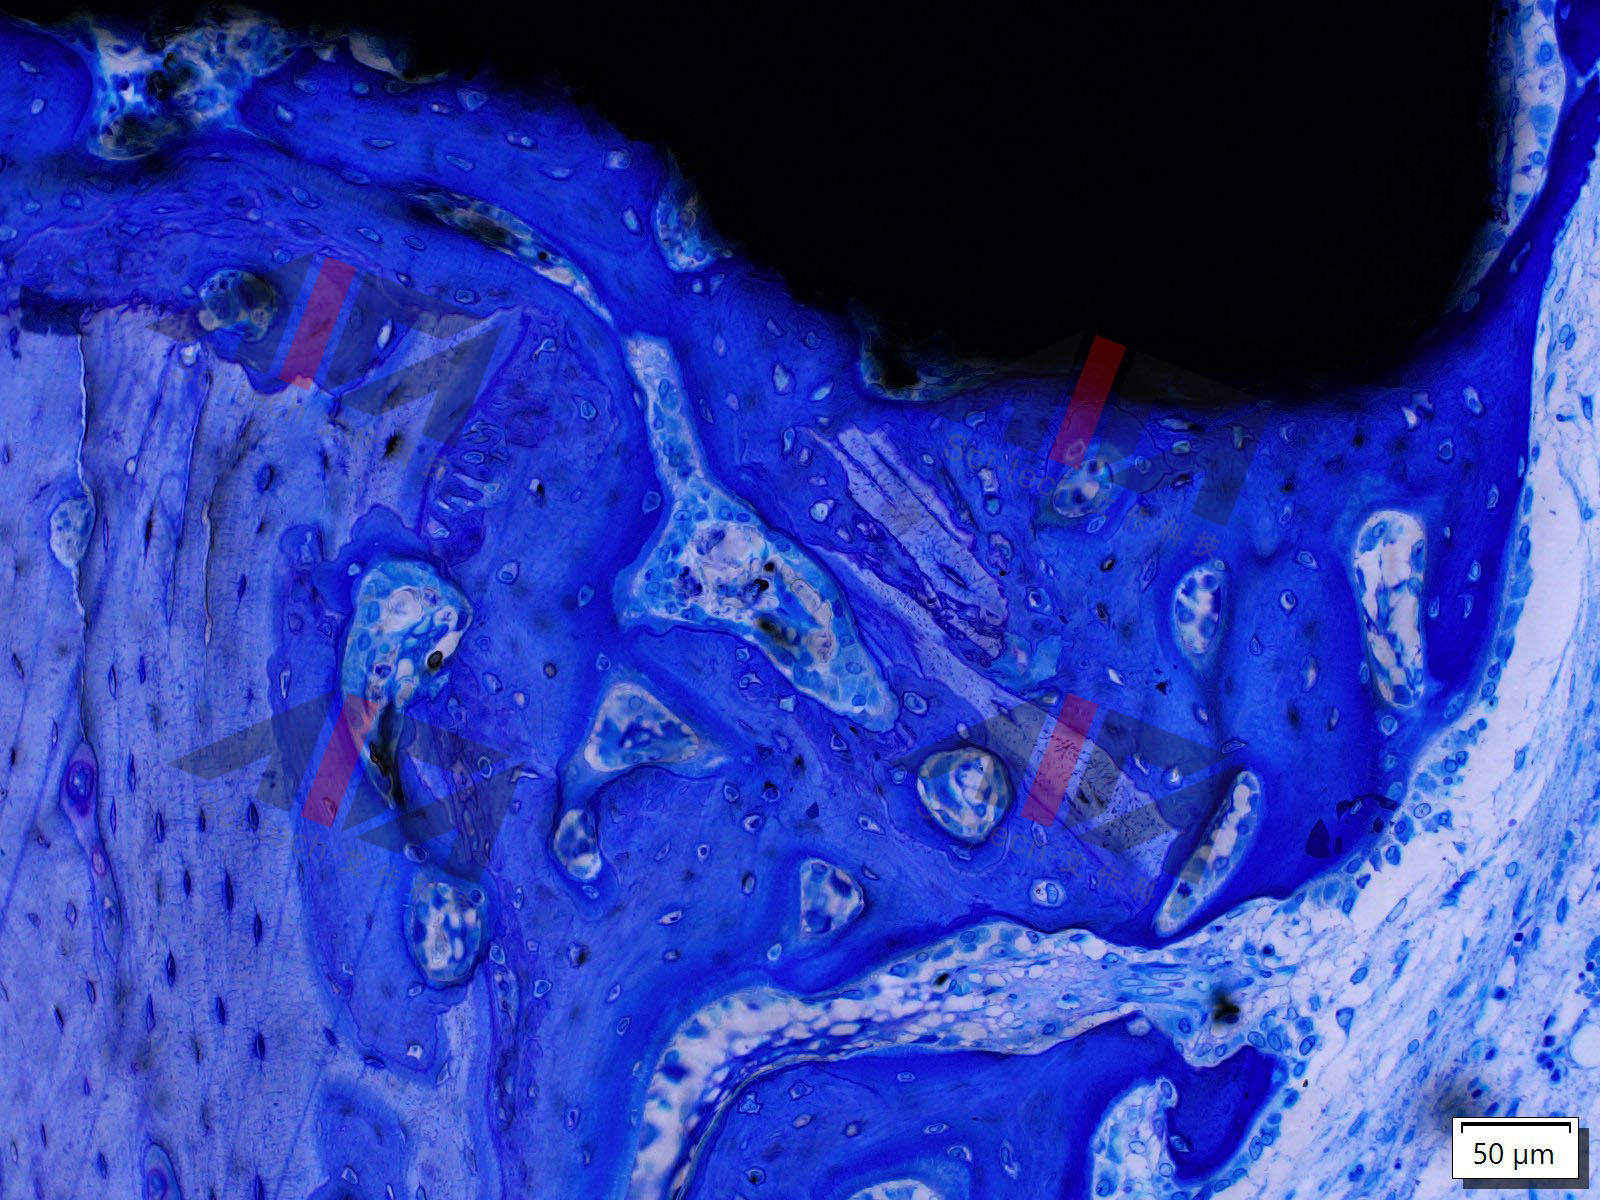

| 经营地址 | 北京市北京经济技术开发区地盛南街1号1幢3041室 | 主要产品 | 制备不脱钙硬组织切磨片,硬组织切磨片染色,制备软组织及脱钙骨切片,软组织与骨切片染色和免疫组化,骨形态计量与分析 |